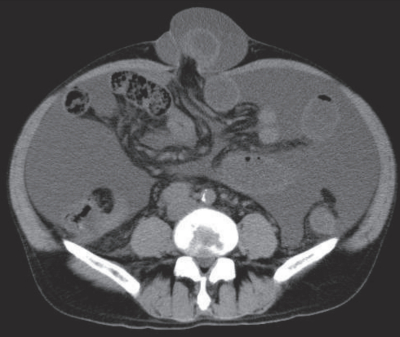

血液所見:赤血球395万、Hb 12.0g/dL、Ht 36%、白血球5,800、血小板9.0万。血液生化学所見:総蛋白5.1g/dL、アルブミン2.1g/dL、総ビリルビン0.5mg/dL、AST 62U/L、ALT 54U/L、LD 252U/L(基準120~245)、ALP 85U/L(基準38~113)、γ-GT 59U/L(基準8~50)、アミラーゼ90U/L(基準37~160)、尿素窒素25mg/dL、クレアチニン1.7mg/dL、血糖195mg/dL、Na 138mEq/L、K 4.8mEq/L、Cl 107mEq/L。CRP 0.2mg/dL。腹部単純CTを別に示す。徒手整復を試みたが成功しなかった。